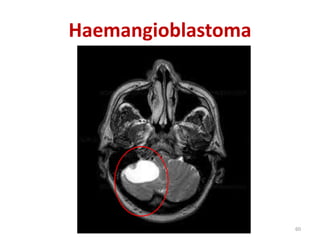

A)Hemangioblastoma:

-Commonest tumor in adult

-More in male

-Benign tumor of vascular origin

-Association: Polycythemia

PRIMARY CEREBELLAR TUMOR:

Haemangioblastoma

A)Hemangioblastoma: -Commonest tumor inadult -More in male -Benign tumor of vascular origin -Association: Polycythemia PRIMARY CEREBELLAR TUMOR: 59